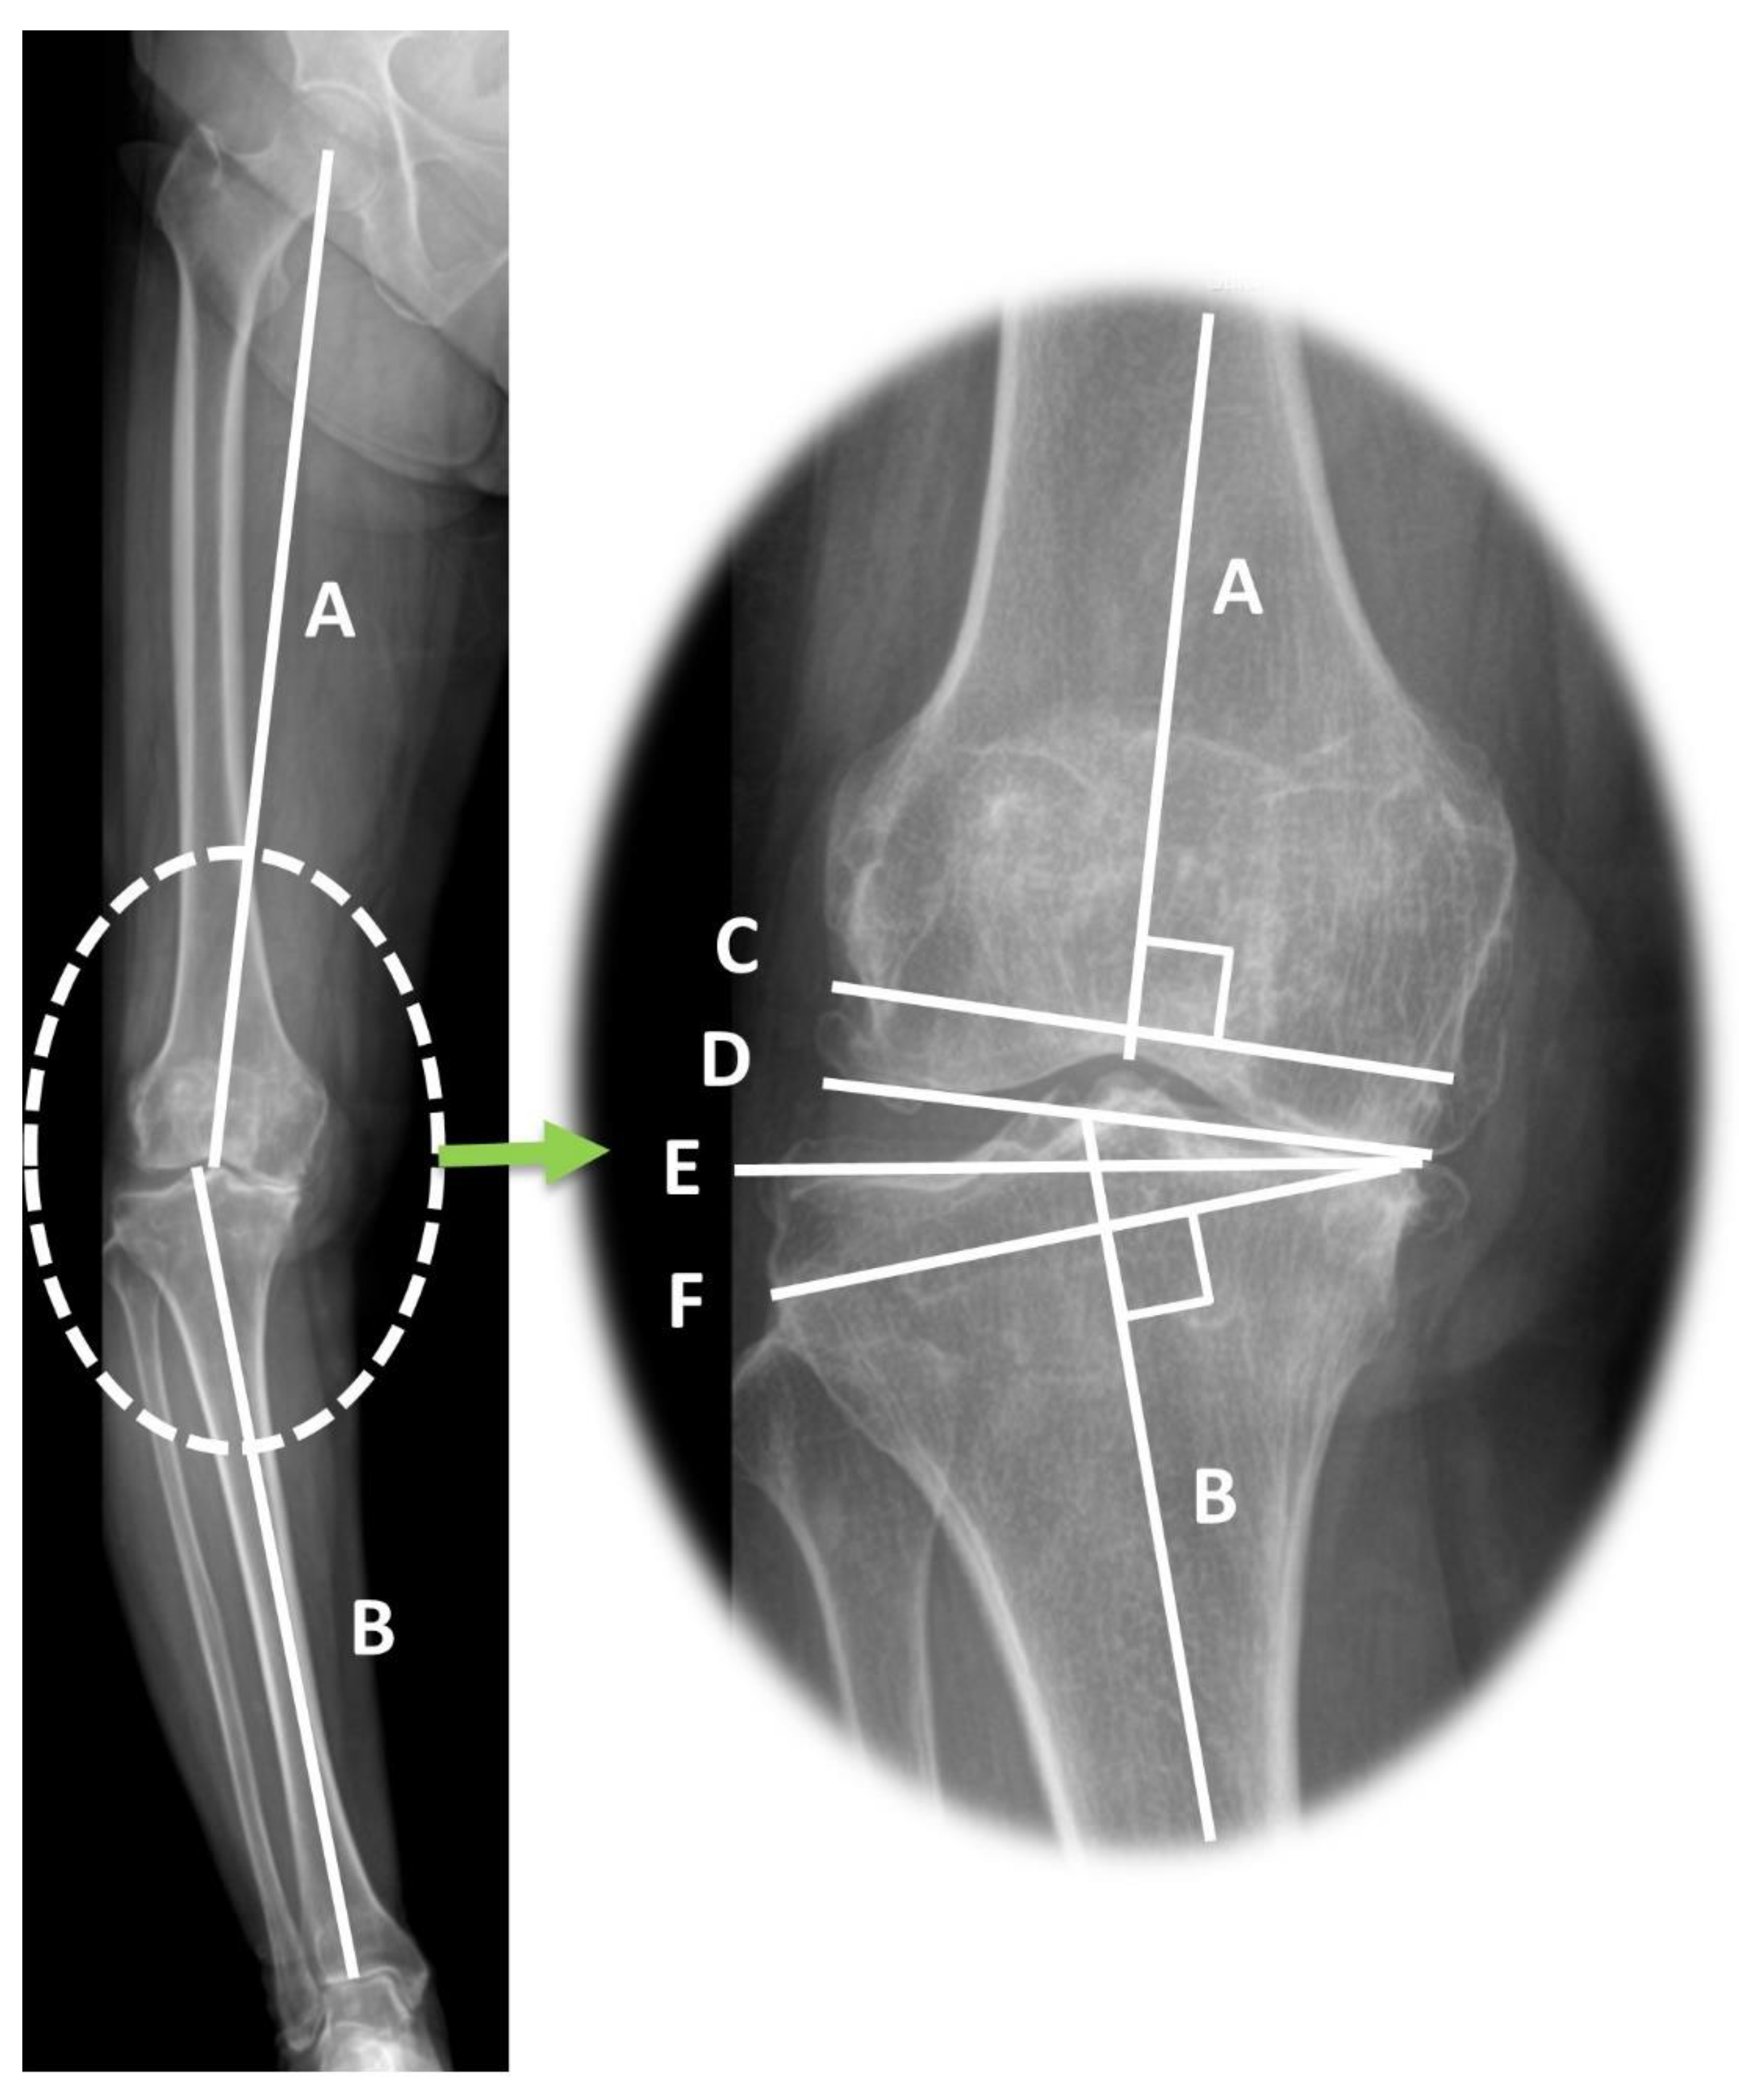

| HKA varus angle (°) | 11.07 ± 4.91 | 6.73 ± 2.27 | 14.33 ± 3.66 | <0.001 |

| mLDFA (°) | 89.81 ± 2.41 | 89.03 ± 2.33 | 90.77 ± 5.06 | 0.001 |

| MPTA (°) | 84.31 ± 3.02 | 85.86 ± 2.40 | 83.14 ± 2.92 | <0.001 |

| JLCA (°) | 5.35 ± 2.48 | 4.16 ± 1.99 | 6.24 ± 2.44 | <0.001 |

| JLCA under varus stress (°) | 7.32 ± 2.80 | 6.88 ± 2.13 | 8.01 ± 3.03 | 0.001 |

| JLCA under valgus stress (°) | 2.28 ± 1.79 | −0.12 ± 2.31 | −0.05 ± 2.30 | 0.805 |